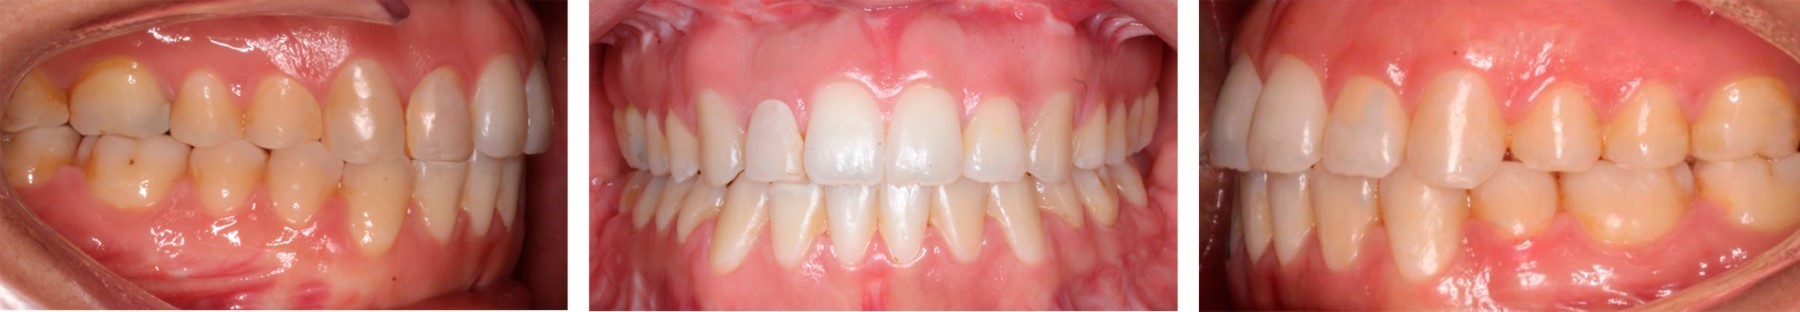

Paciente femenino de 21 años que se presenta en el Centro de Alta Especialidad "Dr. Rafael Lucio", cuyo motivo de consulta es "quiero cerrar la boca bien", no refiere alergias ni malos hábitos. Presenta un biotipo dolicofacial, cara ovalada, línea media facial no coincide con la línea media dental superior, sonrisa gingival de 8 mm y exposición de incisivo en reposo de 6 mm, con un perfil recto, deficiencia del tercio medio facial (Figura 1), mordida borde a borde en el sector anterior, mordida cruzada unilateral derecha posterior, un overjet de 0 mm, clase I canina bilateral, clase I molar derecha y III izquierda por la ausencia del OD 35, apiñamiento leve superior e inferior (Figura 2).

De acuerdo con la evaluación de los estudios radiográficos (Figuras 3 y 4), fotografías extra- e intraorales y datos cefalométricos (Tabla 1) se decide realizar tratamiento ortodóncico-quirúrgico y de esta manera cumplir con los objetivos planeados.